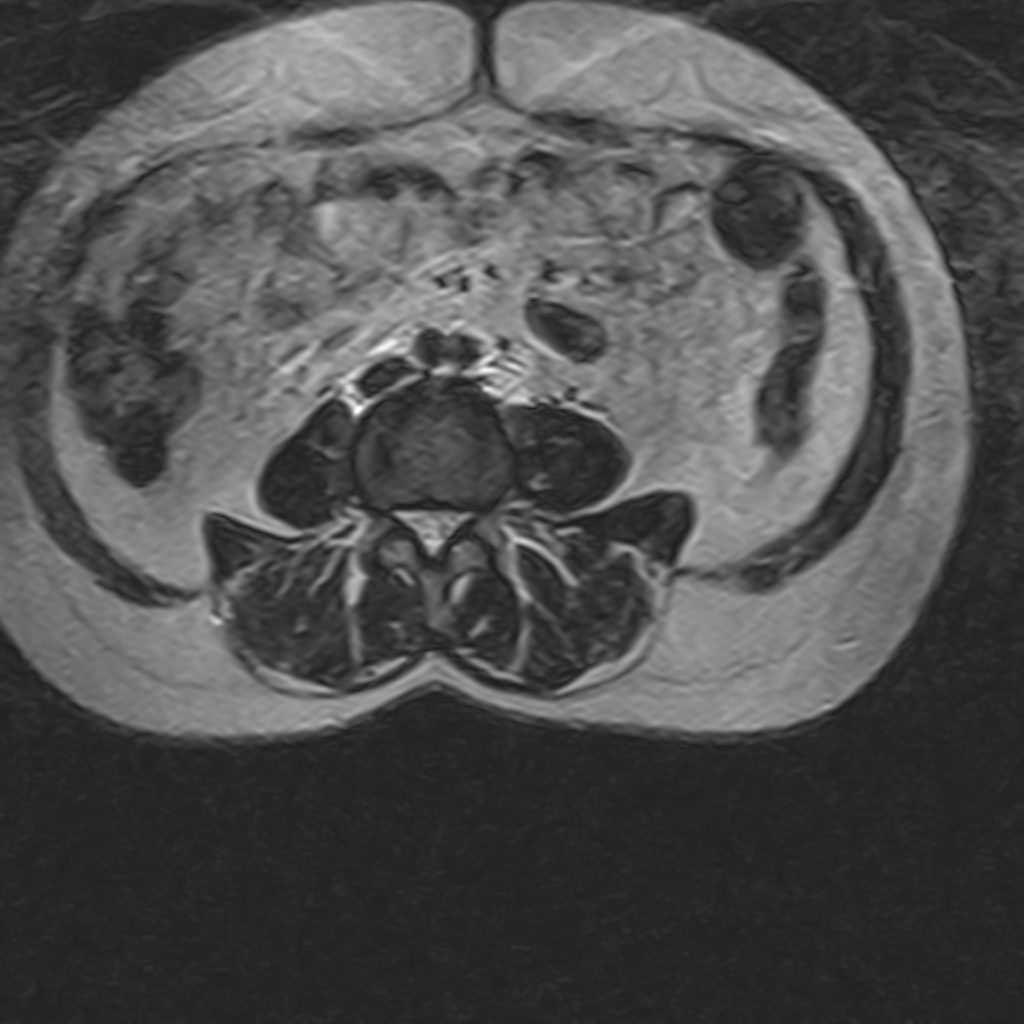

THORACIC & LUMBOSACRAL SPINE MRI

(Without contrast)

Technique : Sagittal T1 , T2 , Axial T2

REPORT:

The vertebral bodies and endplates are normal in shape and signal intensity.

The imaged soft tissues show no abnormalities .

The visualized cord and filum terminalis are normal .

The conus medullaris terminates normally at L1.

Paravertebral stripe is normal in shape and signal intensity .

– Lumbosacral hyperlordosis

– Mid thoracic spondylosis – disc space narrowing , dehydration , bulging & thecal indentation

– L2/L3 disc bulging

– L3/L4 disc space narrowing , dehydration , bulging & foramina stenosis

– L4/L5 disc bulging & canal – foramina stenosis